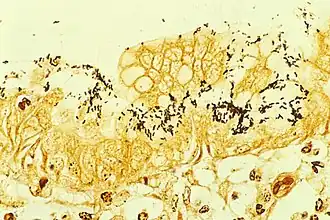

Гистологический метод

Первым методом, который стали использовать для диагностики геликобактерной инфекции, является гистологический метод. Материалом исследования являются клетки тканей, полученных с помощью биопсии, производимой во время эндоскопического обследования желудка и двенадцатиперстной кишки. Специфичность гистологического метода может достигать 100 %, а чувствительность — 91-93 %, ввиду того, что бактерии неравномерно распределены по слизистой оболочке желудка: взятие производится из мест с максимально выраженной гиперемией и отёком, при этом взятие из дна язв и эрозий, а также из их краёв, является ошибкой, поскольку в них нет эпителиальных клеток, необходимых для колонизации бактерий. Кроме того, приём антибиотиков и ингибиторов протонной помпы может трансформировать бактерии из спиралевидной формы в кокковую, которую невозможно выявить с помощью обычной микроскопии[52].